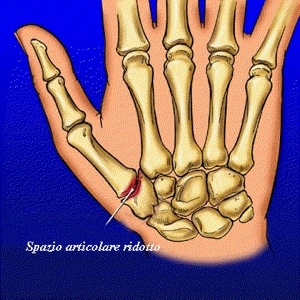

Il portiere, durante l’incontro con la New Team, ha riportato un piccolo ma fastidioso infortunio al pollice della mano e ora potrebbe non recuperare per la prossima gara di Challenge.